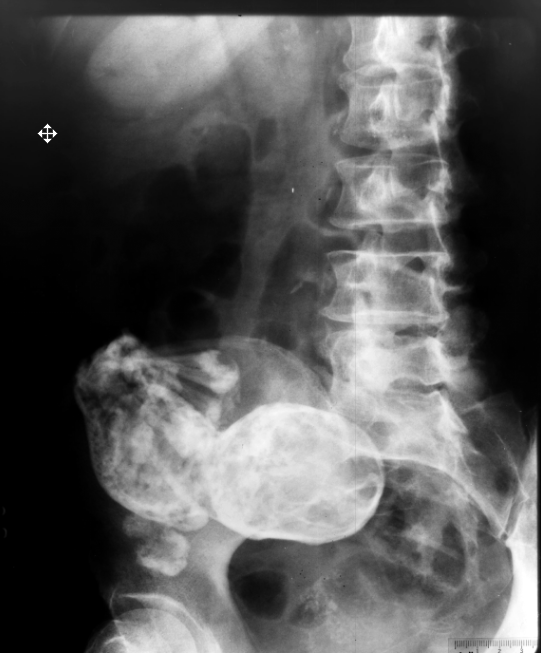

На рентгеновском снимке видны кости, череп, ребра, руки, ноги и позвоночник ребенка.

Данная аномалия, при которой плод "окаменевает" носит название lithopedion, чаще всего случается при внематочной беременности. В медицинской литературе насчитывается не более 300 подобных случаев. Это происходит когда плод умирает, но эмбрион является слишком большим, чтобы быть поглощенным телом. Плод уже сформировался и является для организма слишком большим для поглощения телом. Далее плод кальцифицируется (окаменевает) снаружи, чтобы уберечь мать ребенка от заражения.